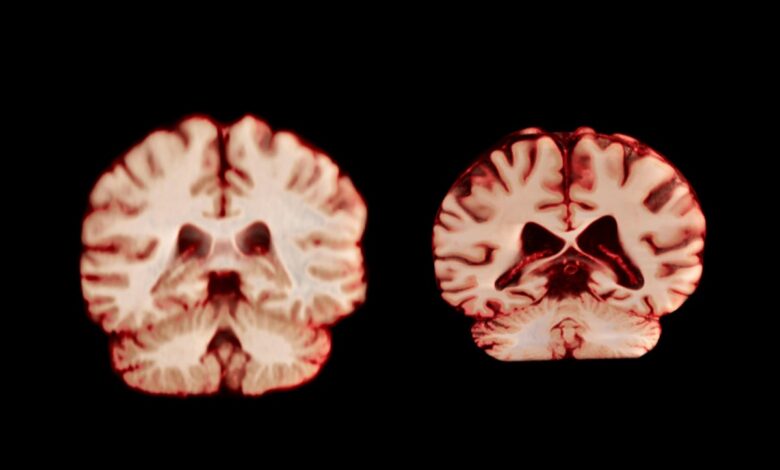

A healthy brain (left) and a brain affected by Alzheimer’s disease.

TheVisualMD/Science Source

During ageing, men experience a greater reduction in volume across more regions of the brain than women do, according to a longitudinal study published today in the Proceedings of the National Academy of Sciences. The authors suggest this means that age-related brain changes do not explain why women are more frequently diagnosed with Alzheimer’s disease than men are.